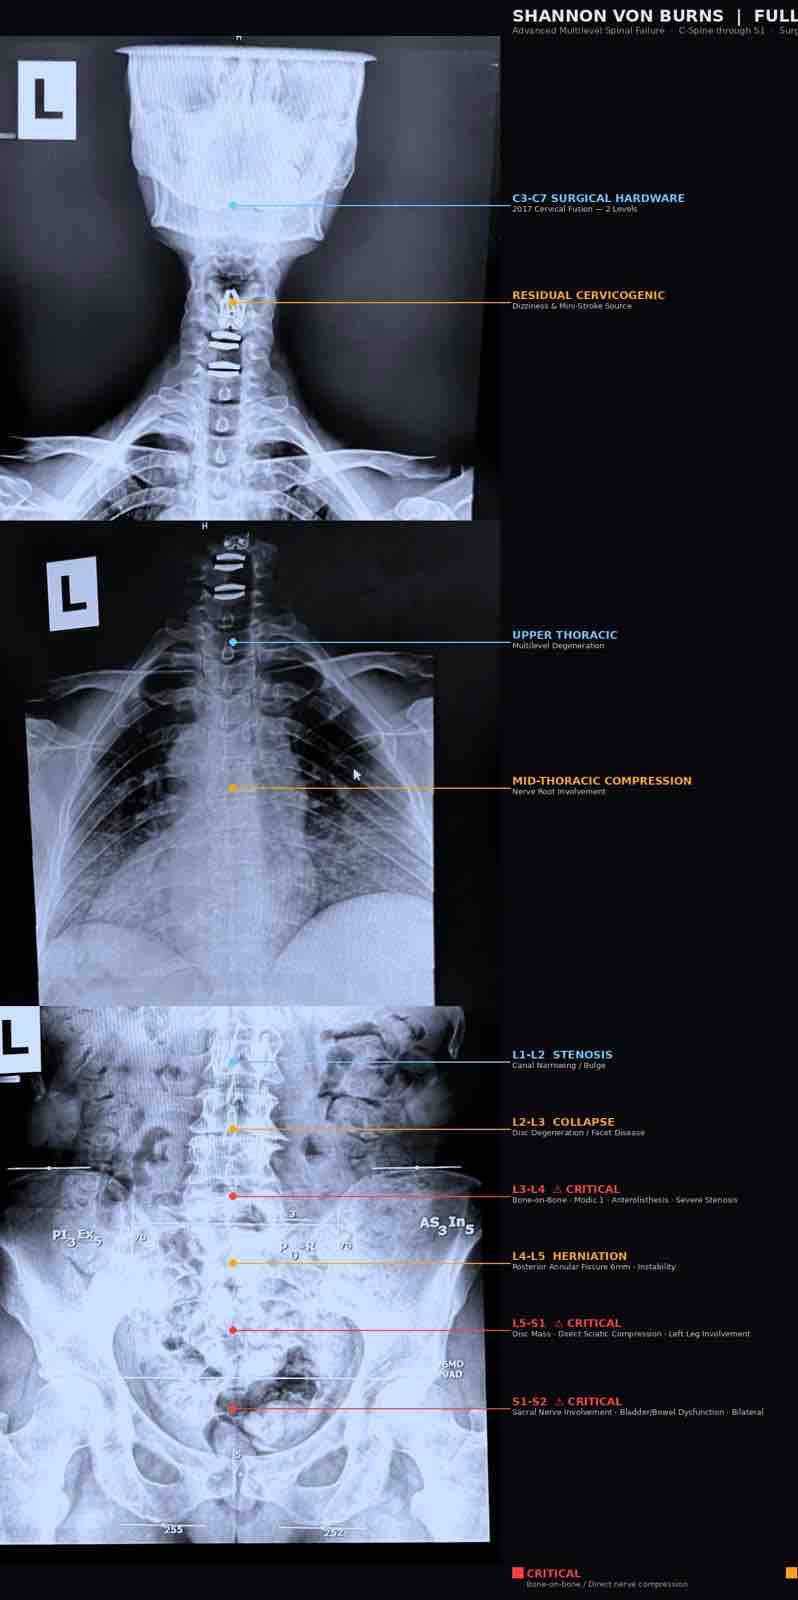

Recent imaging confirms catastrophic failure in her lumbar spine. Two discs are completely gone. Multiple levels have collapsed. Critical nerves are being compressed.

She is now experiencing:

Right foot drop

Both knees buckling without warning

Loss of bladder and bowel control

These are not early symptoms.

They are signs of active neurological damage happening now.

Shannon is scheduled for a two stage spinal reconstruction on April 21st.

The surgery is designed to stabilize her spine, relieve nerve compression, and give her a chance to walk again.